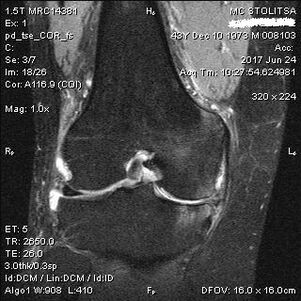

Arthrosis of the knee joint is diagnosed in the rheumatologist's or orthopedist's office.The doctor examines the affected joint, palpates it, listens to complaints and asks additional questions.He performs several tests - for example, he asks the patient to bend the leg or walk a few steps.Then, if it is necessary to clarify the stage of the disease or the nature of the pathological changes, he will refer you to further tests.For example, for computed tomography or radiography.